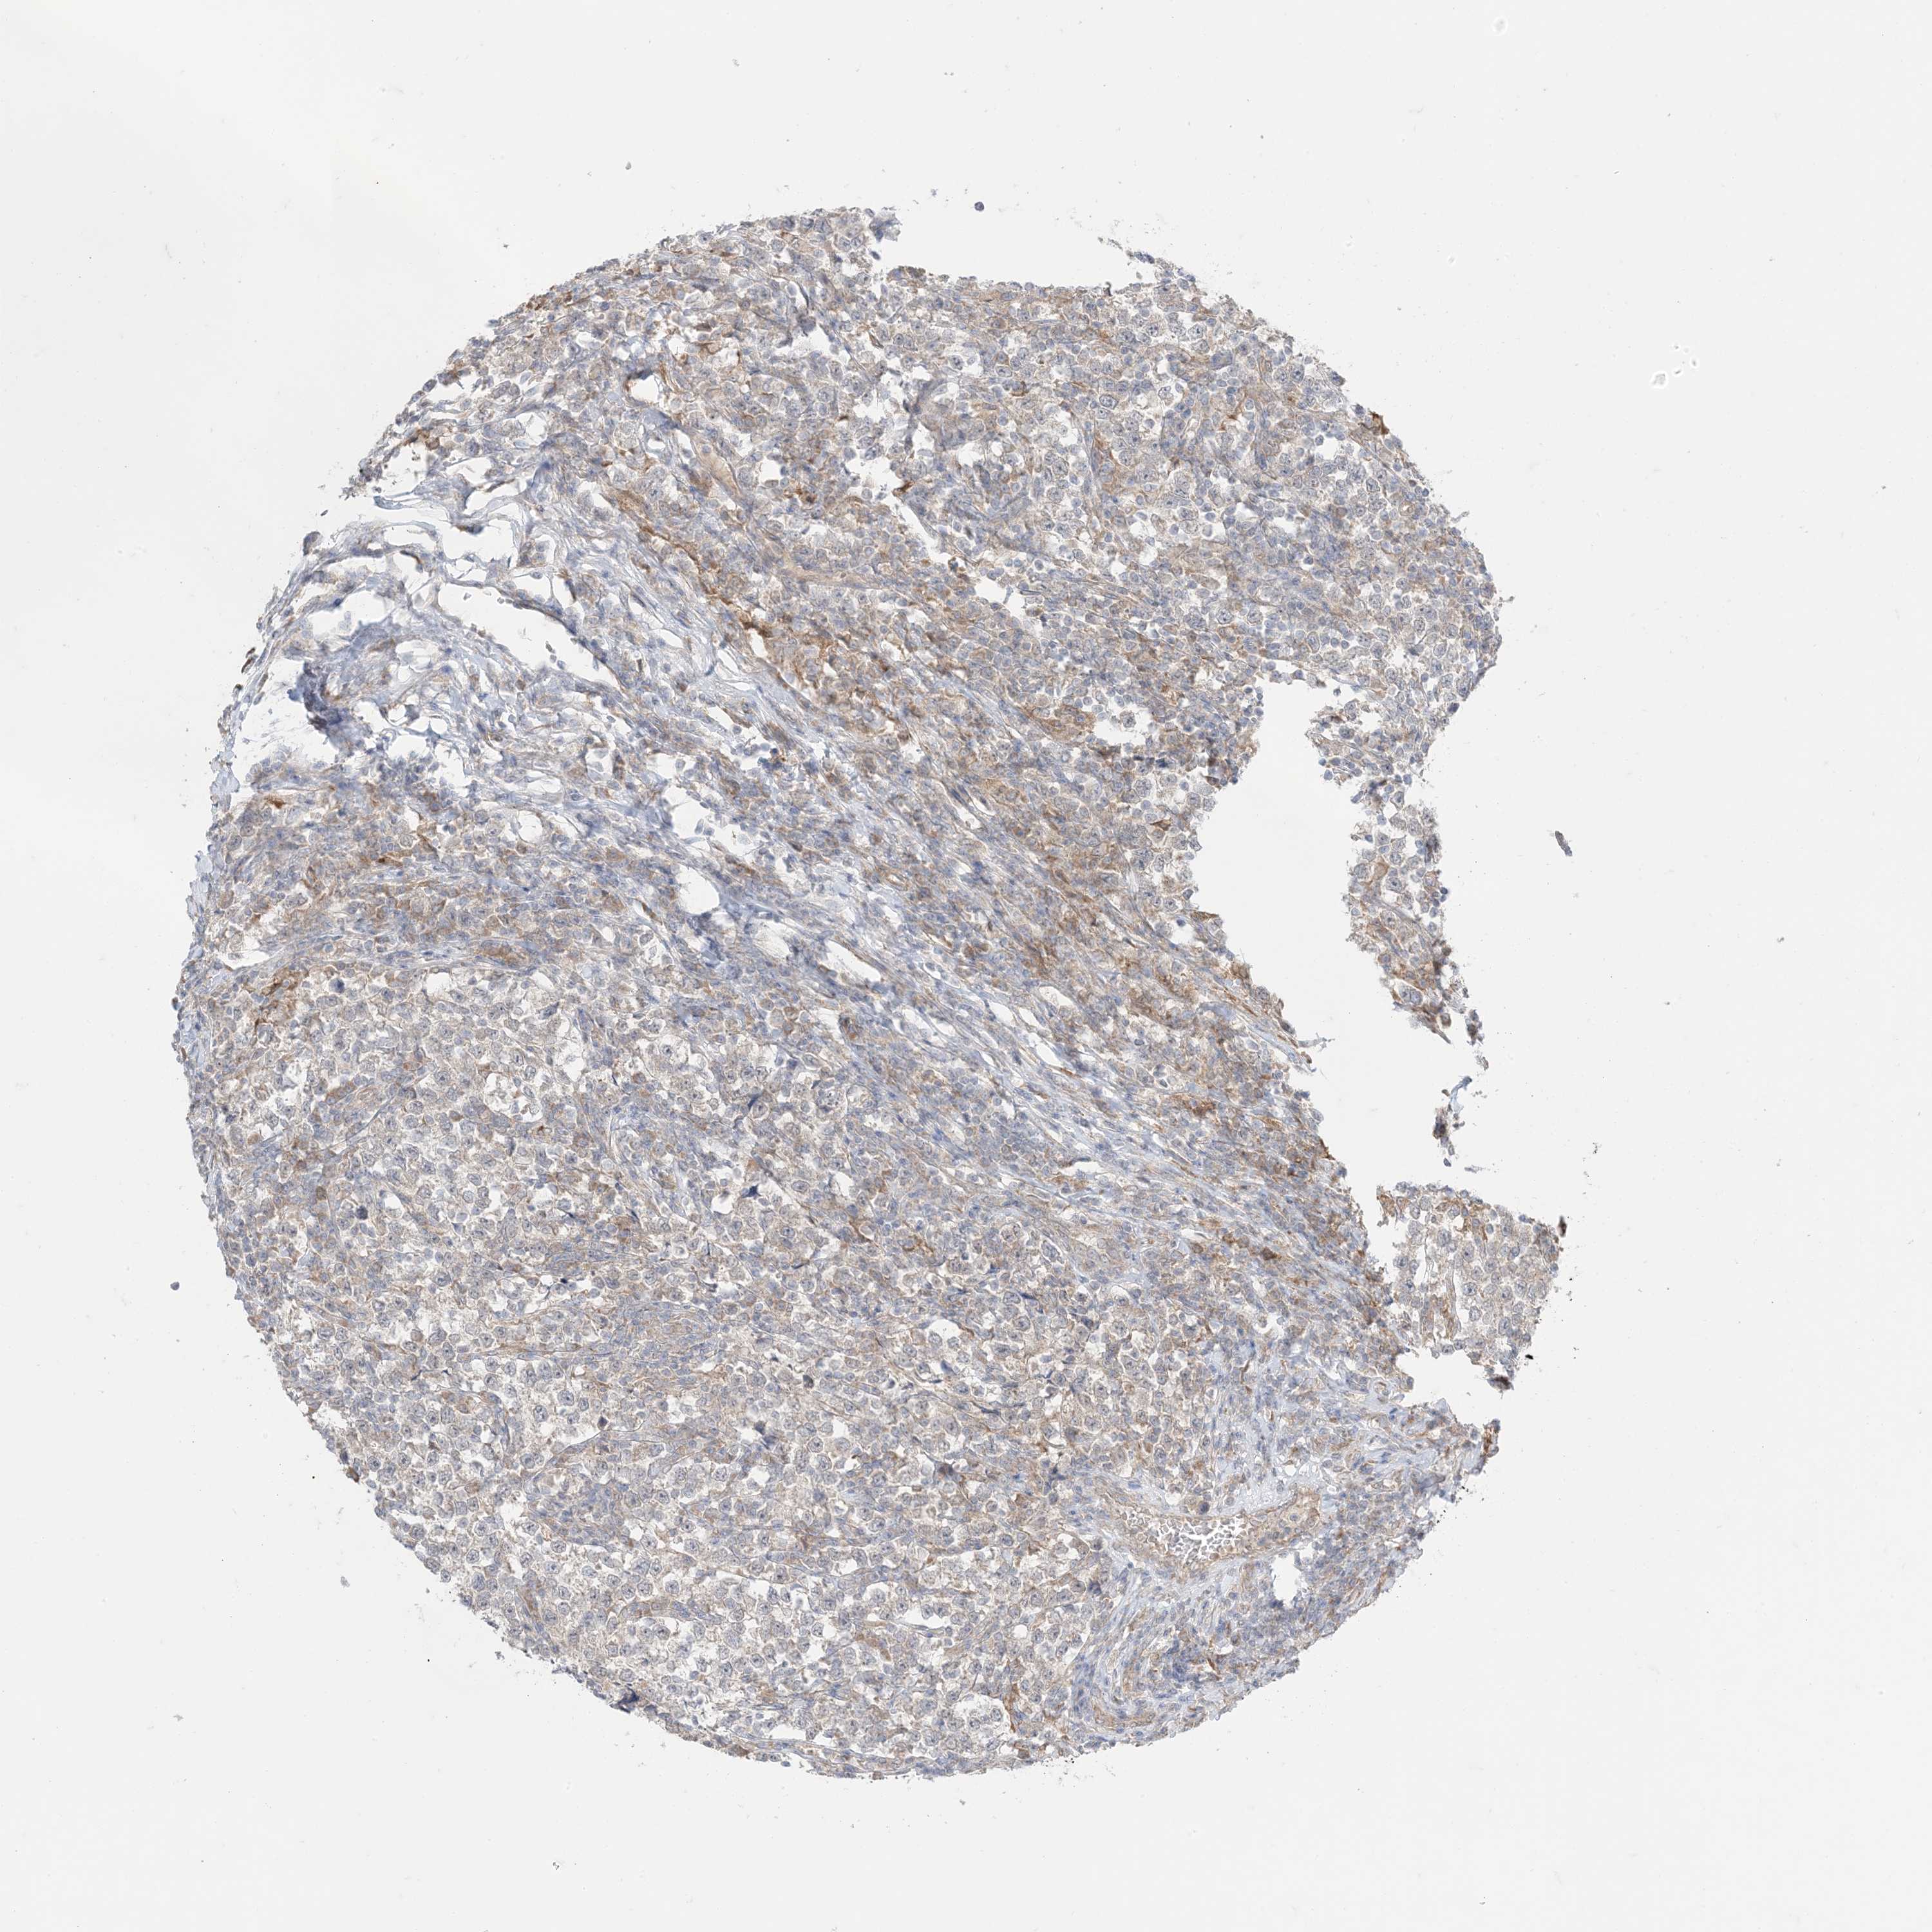

TESTIS CANCER - Protein expressioni

A mouse-over function shows sample information and annotation data. Click on an image to view it in a full screen mode. Samples can be filtered based on level of antibody staining by selecting one or several of the following categories: high, medium, low and not detected. The assay and annotation is described here.

Note that samples used for immunohistochemistry by the Human Protein Atlas do not correspond to samples in the TCGA dataset.

Antibody stainingi

Antibody staining in the annotated cell types in the current human tissue is reported as not detected, low, medium, or high, based on conventional immunohistochemistry profiling in selected tissues. This score is based on the combination of the staining intensity and fraction of stained cells.

Each image is clickable and will lead to virtual microscopy that enables deeper exploration of all samples and also displays staining intensity scores, fraction scores and subcellular localization as well as patient and tissue information for each sample.

Antibody HPA001536

Antibody CAB035996

Staining

High

Medium

Low

Not detected

Intensity

Strong

Moderate

Weak

Negative

Quantity

>75%

75%-25%

<25%

None

Location

Nuclear

Cytoplasmic/membranous

Cytoplasmic/membranous,nuclear

Carcinoma, Embryonal, NOS

Seminoma, NOS

Urothelial carcinoma, High grade